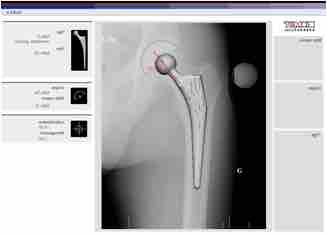

CAD assisted planning for Total Hip Arthroplasty.

For the last 45 years, the most successful and common form of arthroplasty has been the surgical replacement of degenerated joint surfaces with prostheses. For example, a hip joint that is affected by osteoarthritis may be replaced entirely (total hip arthroplasty) with a prosthetic hip. This would involve replacing both the acetabulum (hip socket) and the head and neck of the femur. The purpose of this procedure is to relieve pain, to restore range of motion, and to improve walking ability; thus leading to the improvement of muscle strength.